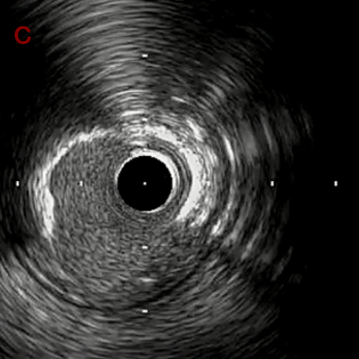

IVUS after OAS high speed 3回

IVUS imaging after high speed 3回

a,b,cはさらに石灰化に食い込み、石灰化量は減少。

それに伴いdではbiasがさらにtentingのIVUS所見にへんかしhigh injury riskと思われた。

引き続き造影で確認してpinpointで引きのOAS high speedを3回さらに追加のためcでIVUSマーキングを行い、その点より引きで赤線のpinpoint OAS high speedを行い、dに関してはinjury回避のためにOASを当てない方針とした。